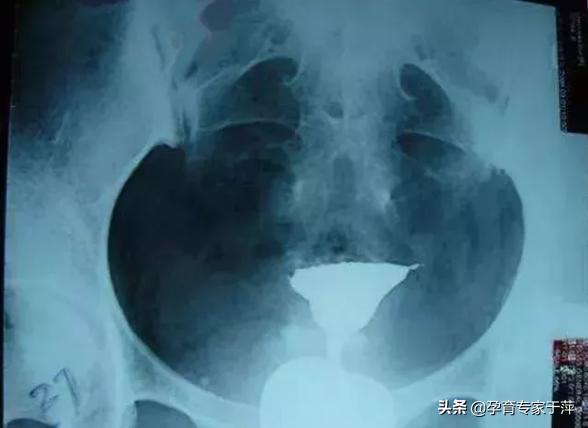

输卵管造影就是将造影剂注射到子宫腔内,造影剂可以经过输卵管进入盆腹腔内,在X线下可以清晰地看到子宫腔及两侧的输卵管的形态,是否通畅,是堵塞、黏连还是通而不畅,病灶的位置等都能清晰的看到。子宫输卵管造影术是输卵管通畅度的一线筛查手段。

患者做完造影后都是需要医生来根据造影片子来解读输卵管的通畅性的,虽然这属于比较专业的范畴,但在这里我也给大家列举几个典型的片子给大家一些参考。

5、输卵管积水

造影片的表现是一侧或双侧输卵管远端增粗、膨大,呈“腊肠状”。这是由于输卵管远端粘连不通导致输卵管内造影剂不能溢出所导致。所以,输卵管积水的前提是输卵管不通。如果造影片显示输卵管伞端有造影剂溢出就不是积水。